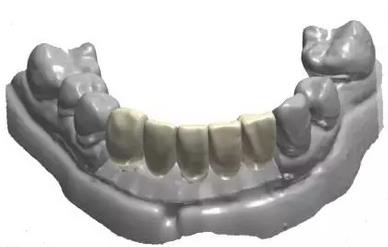

牙支持式導(dǎo)板生成

手術(shù)導(dǎo)板數(shù)據(jù)發(fā)送至成都登特,通過(guò)BEGO打印機(jī)打印出導(dǎo)板,切削出臨時(shí)冠